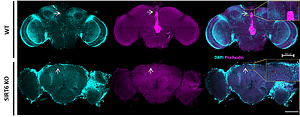

صورة مجهرية: في الصف العلوي - صورة لدماغ ذبابة طبيعية، وفي الصف السفلي - دماغ ذبابة مصابة بالتنكس العصبي، يظهر ثقوبًا في الدماغ. حقوق الصورة: شاي كلوكسي-